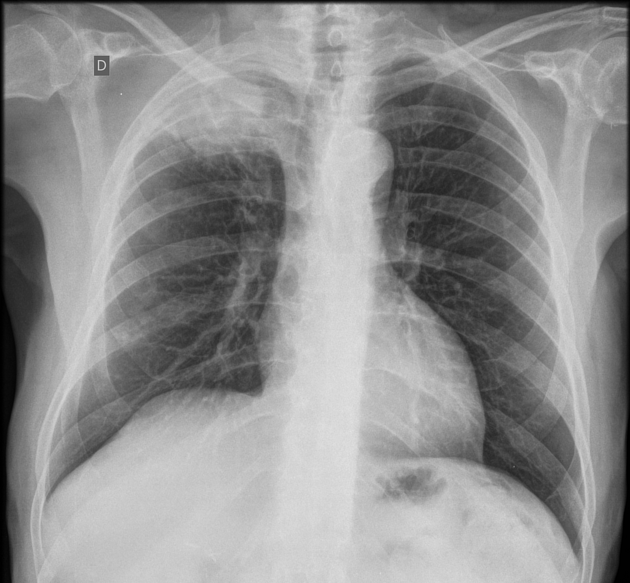

Puzzle 63

What's the Diagnosis?

Guess 1 / 5